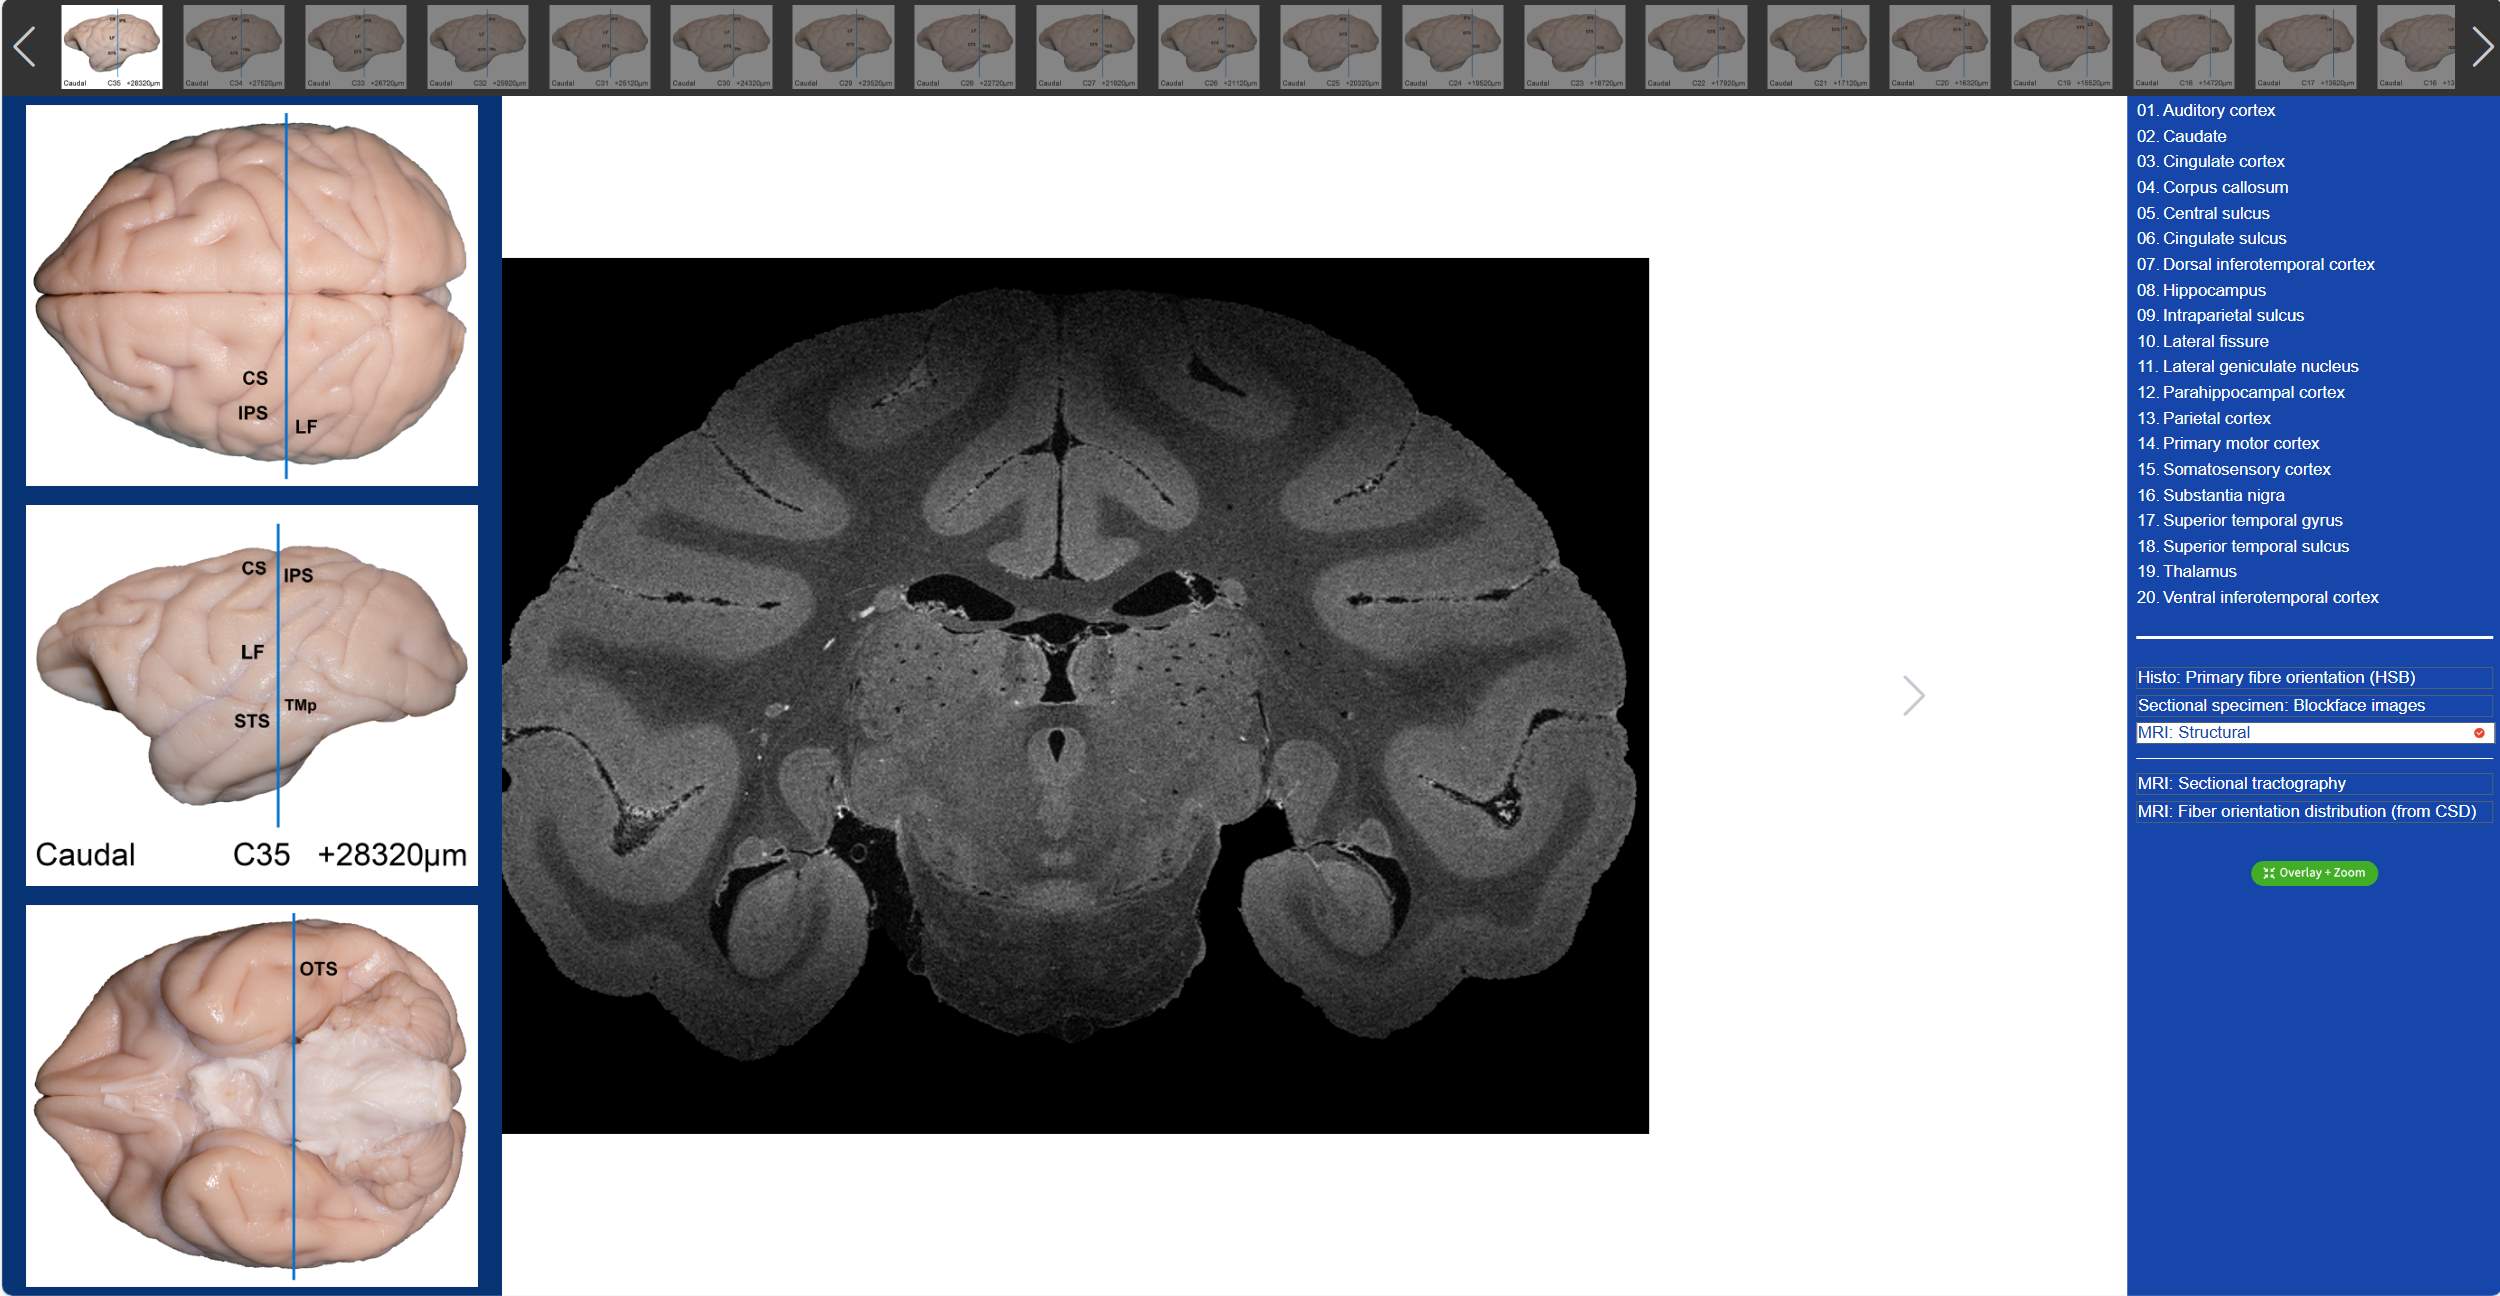

“动物脑乐园”是由复旦大学神经外科研究所脑功能实验室创建的一个科普网站,运用先进的三维摄像技术,展示了猕猴大脑以及人脑,猪脑,羊脑等共十二种动物的脑标本,使我们可以突破时间和空间的限制,随时随地学习解剖学知识,直观的了解和感受大脑的性状,质地等信息,避免只见树木不见森林的困境,在大脑三维展示界面,我们可以通过鼠标或触控板来旋转,缩放每一个动物的脑标本,从任何一个角度进行观察,就像该脑标本在我们面前一样,直观的感受不同动物大脑的性状和大小,并与人脑进行比较,在人类大脑三维展示界面,我们不仅可以细致的观察到每一条沟回,还可以通过点击相应区域的编码,查看其位置和负责的功能 91抖音短视频APP,从而加深对大脑结构的理解。

值得一提的是,在“动物脑乐园”里,不仅可以观察到猕猴3D脑标本,还可以看到猕猴的全脑切片,吴劲松教授团队从同一猴脑的离体MRI及全脑组织切片髓鞘染色(LFB)数据集中,间隔800μm取一层,构建了集合组织切片髓鞘染色(LFB),组织切片髓鞘染色-伪彩化,断层标本图,高分辨率MRI结构像及离体脑dMRI断层纤维束成像和纤维方向分布图(限制球面反卷积-CSD)六大模态的断层对照图谱 91抖音免费观看,我们只需要点击相应的解剖名称,就可以在图谱上对应位置显示标记,同时可与另外两大模态的dMRI方向性信息进行对照,极大的方便了我们的观看。